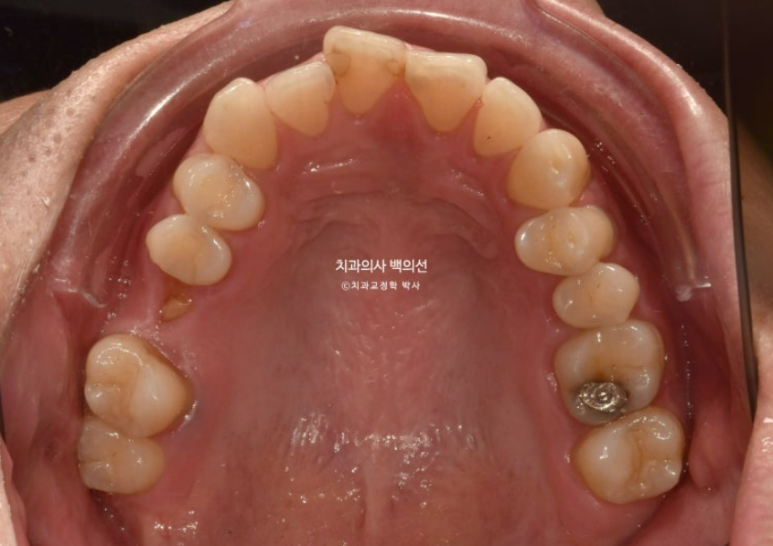

초진 정밀진단에서 확인되는 문제가 하나 더 있습니다.

앞니 사이의 과잉치입니다. 정가운데 위치한 과잉치를 정중과잉치 라고 합니다.

CT를 찍어 확인하니 과잉치의 위치가 신경관과 가깝고 깊어서 빼기가 쉽지 않습니다.

다행인점은 앞니의 이동을 최소화 하면 굳이 과잉치를 안 빼고도 교정치료가 가능한 상태라는 것입니다.